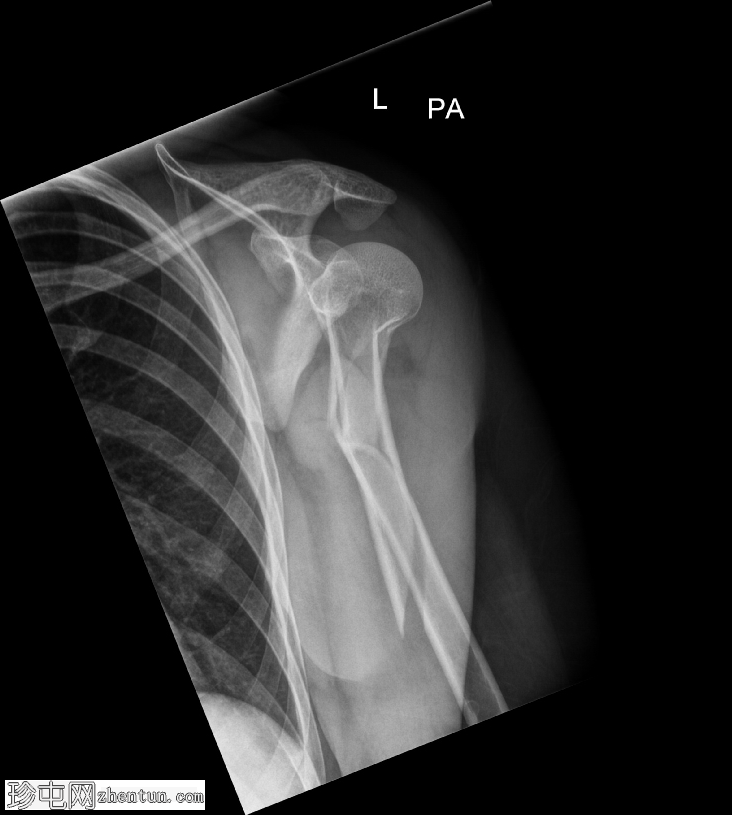

斜位

肱骨近端粉碎性移位骨折,累及骨干近端半部、外科颈,并延伸至大结节。

肱骨头在肩关节内向下半脱位,肩峰肱骨间距增大。

肱骨头向下移位(假性半脱位)是肱骨近端骨折常见的继发性表现。它提示关节积液、关节积血或暂时性关节囊松弛,而非肩关节真正的不稳。手臂负重和肌肉张力下降(尤其是三角肌和肩袖肌群)共同导致肱骨头相对于肩胛盂位置下移<sup>1-3</sup>。

这种表现不应与真正的肩关节脱位混淆,因为在Y形位或轴位影像上,肱骨头仍与肩胛盂保持正确的对位。随着关节液的吸收和肌肉张力的恢复,这种情况通常会自行缓解。识别这种暂时性的良性表现对于避免不必要的复位手术至关重要。

在本病例中,肱骨头位置下移反映了由急性近端肱骨骨折引起的关节积液所致的假性半脱位,而没有真正的脱位证据。